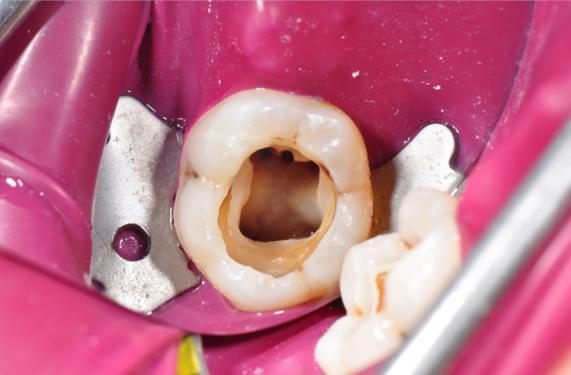

3、发现蛀牙了,带孩子去牙科诊所去检查蛀牙情况,近期会换的蛀牙,就不用去治疗跟修补了,近两三年都不会换的,要进行及时的治疗,防止蛀牙损伤要牙根。

尽量选择正规的牙科诊所,离家比较近的进行治疗,治疗牙齿不是一天两天就能解决好的,需要一个月或者需要更长时间。